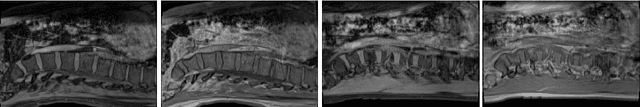

Abstract:Domain adaptation (DA) has drawn high interests for its capacity to adapt a model trained on labeled source data to perform well on unlabeled or weakly labeled target data from a different domain. Most common DA techniques require the concurrent access to the input images of both the source and target domains. However, in practice, it is common that the source images are not available in the adaptation phase. This is a very frequent DA scenario in medical imaging, for instance, when the source and target images come from different clinical sites. We propose a novel formulation for adapting segmentation networks, which relaxes such a constraint. Our formulation is based on minimizing a label-free entropy loss defined over target-domain data, which we further guide with a domain invariant prior on the segmentation regions. Many priors can be used, derived from anatomical information. Here, a class-ratio prior is learned via an auxiliary network and integrated in the form of a Kullback-Leibler (KL) divergence in our overall loss function. We show the effectiveness of our prior-aware entropy minimization in adapting spine segmentation across different MRI modalities. Our method yields comparable results to several state-of-the-art adaptation techniques, even though is has access to less information, the source images being absent in the adaptation phase. Our straight-forward adaptation strategy only uses one network, contrary to popular adversarial techniques, which cannot perform without the presence of the source images. Our framework can be readily used with various priors and segmentation problems.

Abstract:We propose to adapt segmentation networks with a constrained formulation, which embeds domain-invariant prior knowledge about the segmentation regions. Such knowledge may take the form of simple anatomical information, e.g., structure size or shape, estimated from source samples or known a priori. Our method imposes domain-invariant inequality constraints on the network outputs of unlabeled target samples. It implicitly matches prediction statistics between target and source domains with permitted uncertainty of prior knowledge. We address our constrained problem with a differentiable penalty, fully suited for standard stochastic gradient descent approaches, removing the need for computationally expensive Lagrangian optimization with dual projections. Unlike current two-step adversarial training, our formulation is based on a single loss in a single network, which simplifies adaptation by avoiding extra adversarial steps, while improving convergence and quality of training. The comparison of our approach with state-of-the-art adversarial methods reveals substantially better performance on the challenging task of adapting spine segmentation across different MRI modalities. Our results also show a robustness to imprecision of size priors, approaching the accuracy of a fully supervised model trained directly in a target domain.Our method can be readily used for various constraints and segmentation problems.